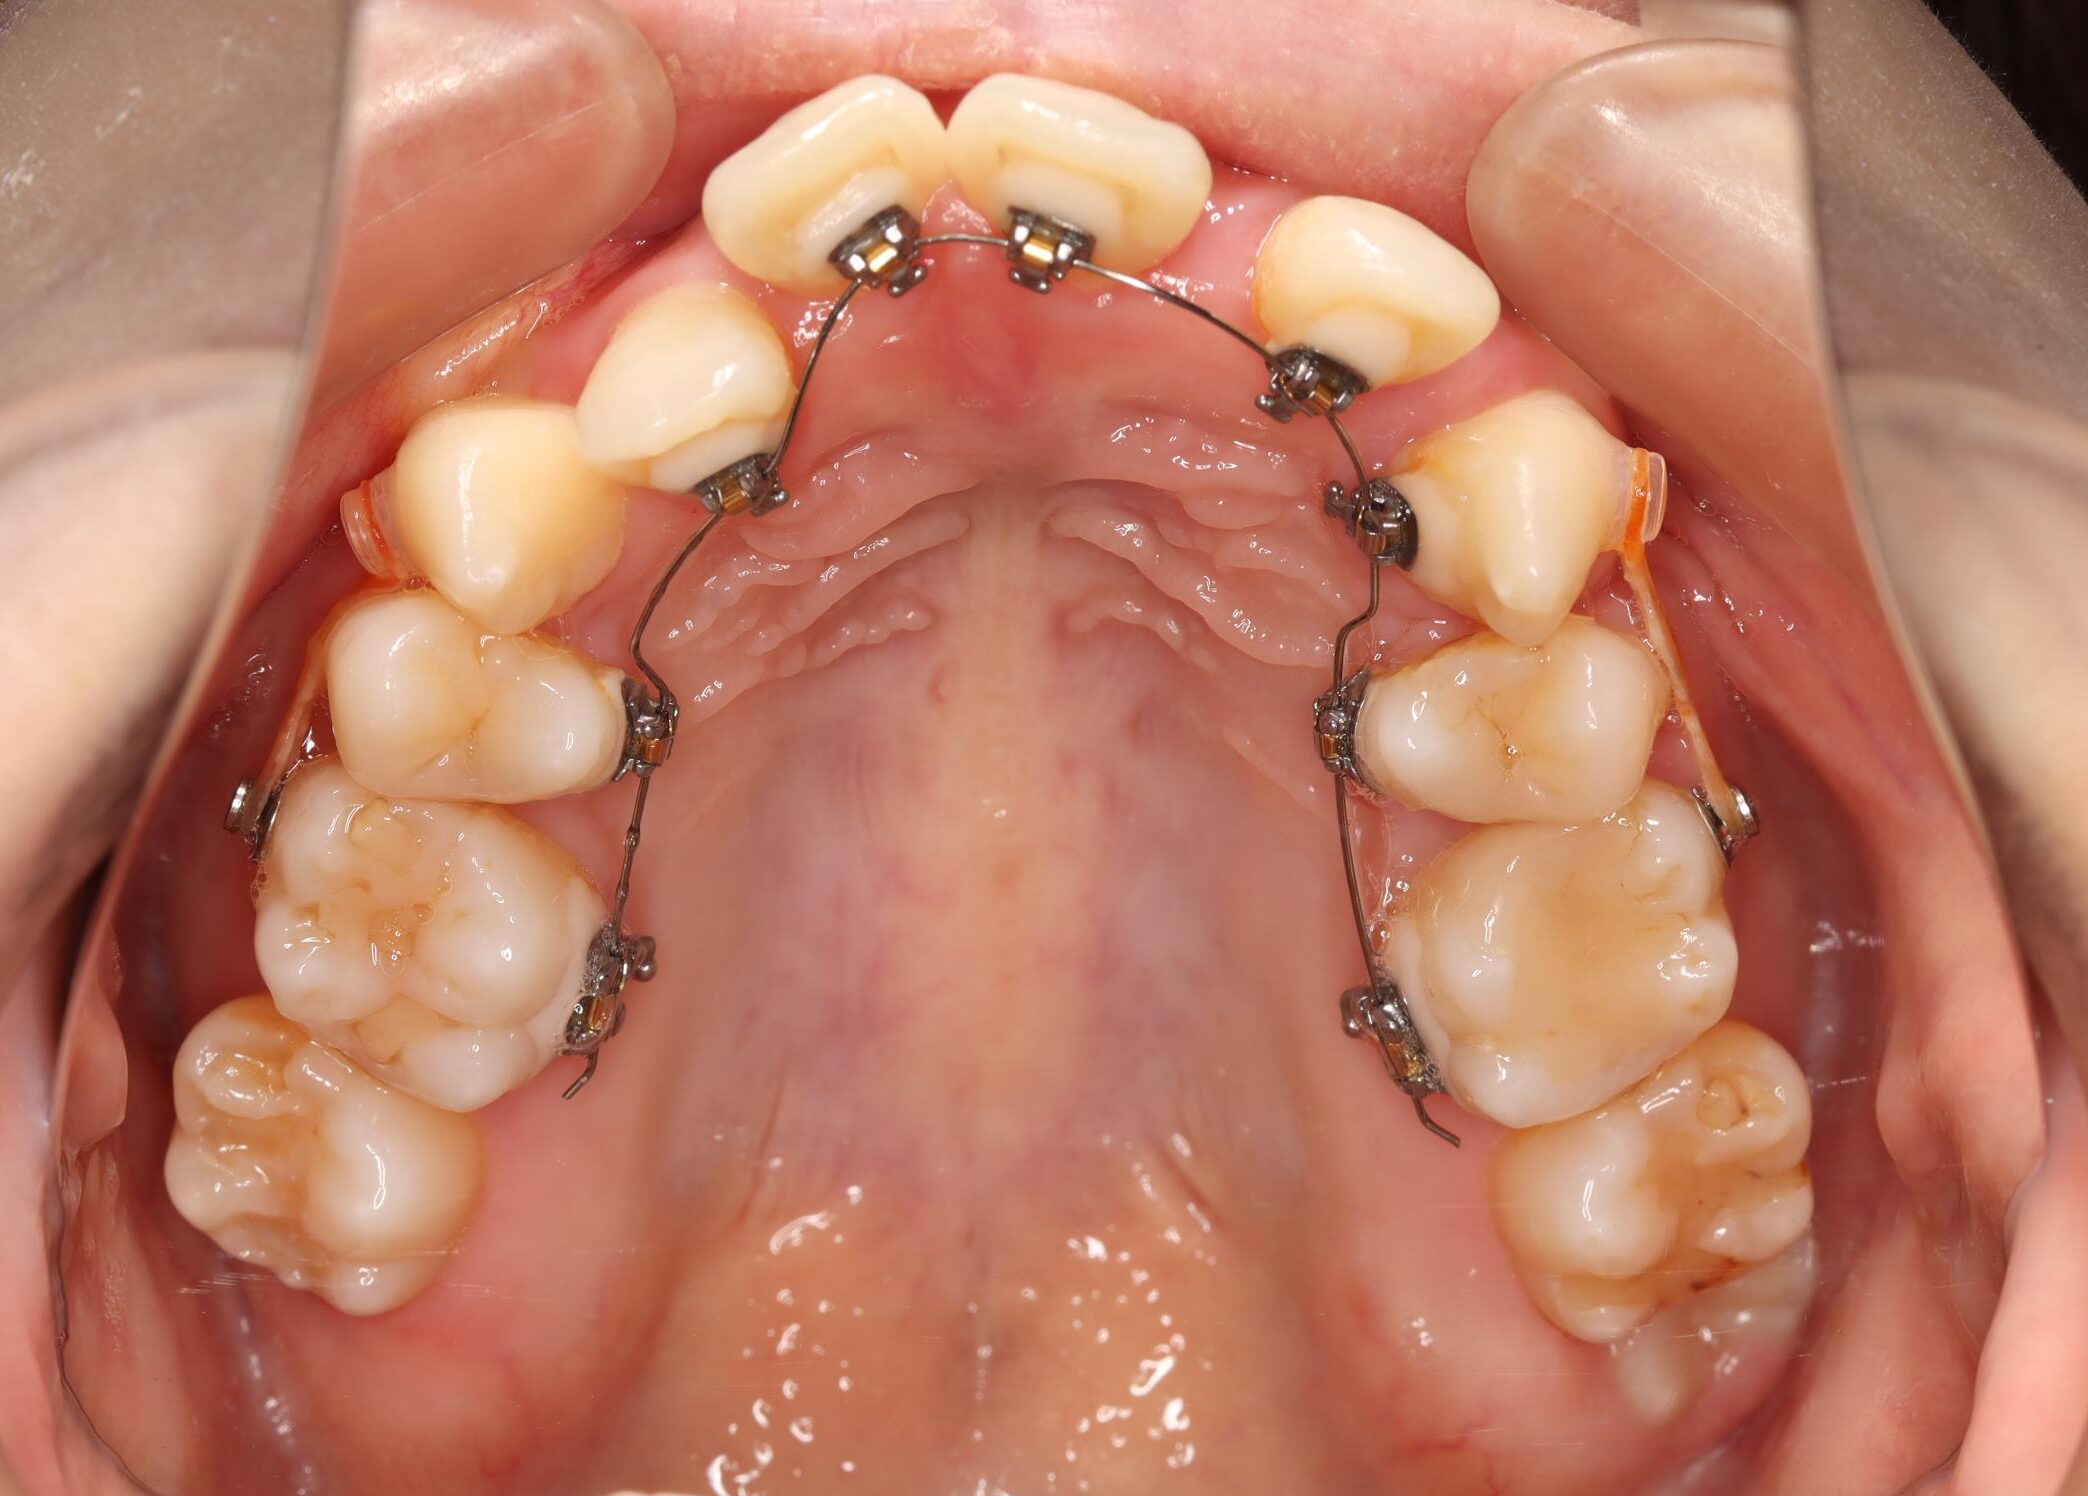

治療中

| 使用矯正装置 | セルフライゲーションリンガルブラケット 歯科矯正用アンカースクリュー |